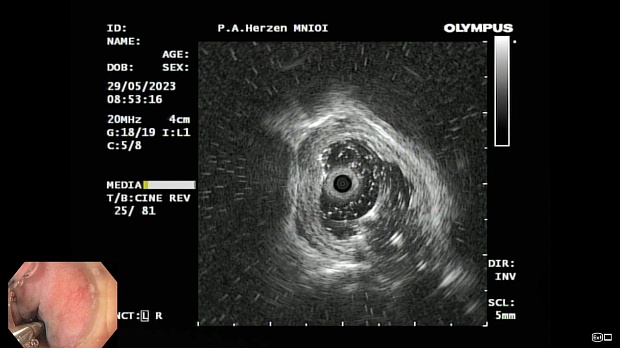

Иллюстрация №3: Эндофото. Сидероз нижней трети пищевода, эндоскопическая ультрасонография

Согласно полученным данным - в среднегрудном и нижнегрудном отделах пищевода определялась проксимальная граница плоских неправильной формы поверхностных рубцов суммарной протяженностью до 8,0 см. На этом фоне в зонах поверхностных рубцов по задней полуокружности визуализировались участки гиперпигментации в темный цвет (Рис. 1). При исследовании в режиме Dual Focus было отмечено наличие мелких (до 0,001 см) черно-коричневых включений, расположенных субэпителиально - в строме слизистой оболочки, сливания их в единый конгломерат не определялось (Рис. 2). При эндосонографии с применением минидатчика с частотой сканирования 20МГц выявлено, что все слои стенки четко дифференцируются, не утолщены, в слизистой оболочки визуализированы мелких гиперэхогенные включения с эхотенями (Рис. 3).